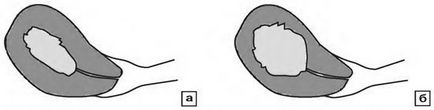

Reakcióvázlat értékeli a mértékét invázió endometriális rák:

és - a mélysége invázió 50%; b - a fertőzöttség, hogy a mélysége több mint 50%